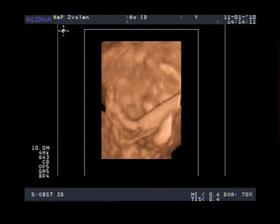

- 10.12.09 - morfologicke utz. ..... podla p. doktora je malicke v poriadku, vazime 300g 🙂